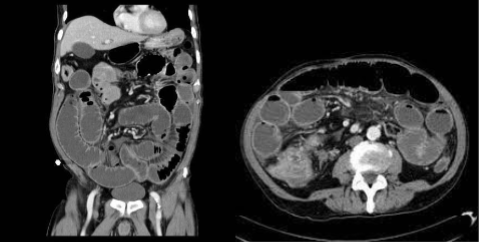

Diverticulosis, CT

What is this and what type of scan